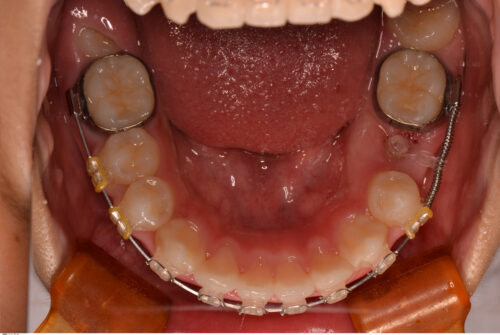

スペースができたら粘膜を切開して装置を接着しゴムで引っ張ります。

ある程度出てきたら装置を付け換えてきれいに並ぶよう位置を修正していきます。